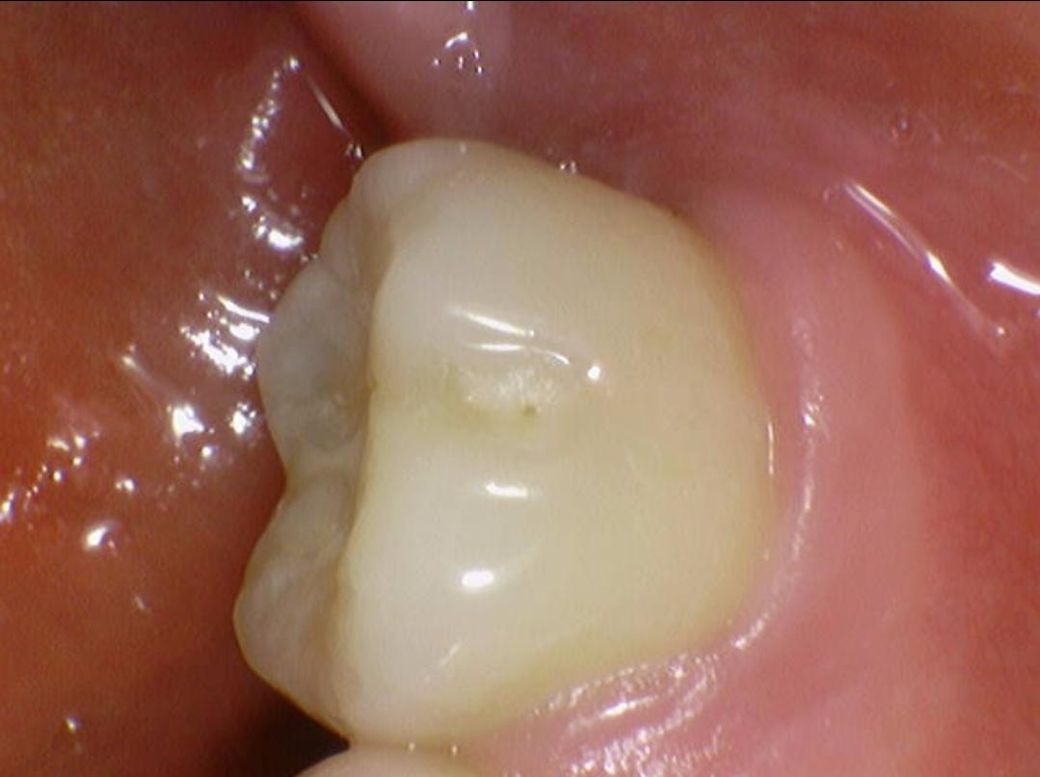

여쭙고 싶은건 깨진건(이 일부가 떨어져나감) 저도 보이기는 하는데

이게 시간이 지날수록 발치가 이어질 안좋은 크랙인지, 아니면 일단 10년 정도는 조심스럽게 그냥 살아도 괜찮은, 흔한 경우인지 입니다

밑에 구강내부 사진(16,17,26,27번 치아)들에서

치료가 반드시 필요한 치아는 몇번째 사진 이런식으로 설명 부탁드립니다

두번째가 깨진 부분들 다 인접면 충치라고 그러던데 다른치과에서 찍은 교익 방사선,파노라마,사진들 모두(각자 다른 치과) 고려했을때 법랑질 뚫고 간 흔적이 안보여서 판독 부탁드리려고 합니다

정말로 인접면 충치인지요..

• 2번 째 사진

파절된 부위가 보이긴 합니다 하지만 금이 깊게 진행될 정도로 보이는 것은 아닌 것으로 판단이 됩니다 정확한 확인은 직접 확인을 해 봐야 알 수 있습니다.

예전에 치아 사이에 레진치료를 한곳이 떨어진 부분이 몇군데 잇는거 같습니다. 작은 사진을 찍어보시고 치료를 받으시는게 좋을것같습니다.

3. 사진상으로 추가적으로 확인해봐야할 치아는 #16, #25, #26, #36, #46 입니다